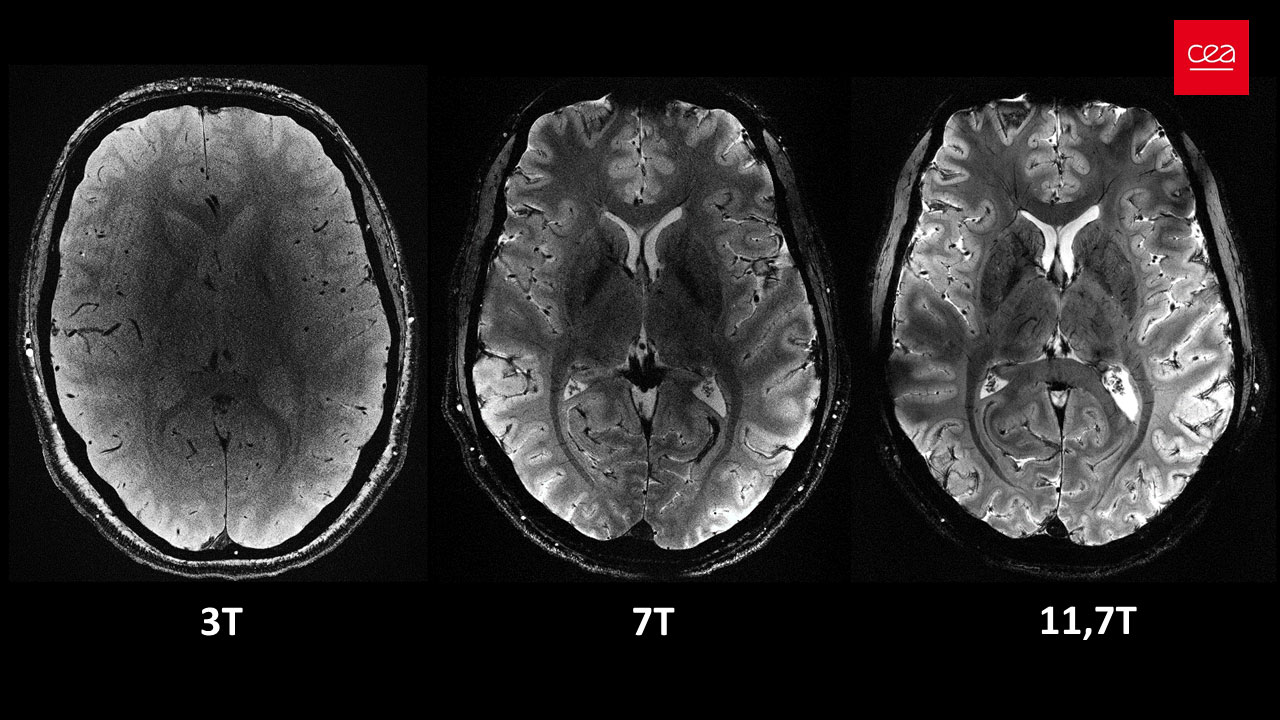

Το CEA αποκαλύπτει μια σειρά από in vivo εικόνες ανθρώπινου εγκεφάλου που αποκτήθηκαν με το μηχάνημα μαγνητικής τομογραφίας Iseult και την απαράμιλλη ένταση μαγνητικού πεδίου 11,7 teslas. Η επιτυχία αυτή είναι ο καρπός περισσότερων από 20 ετών έρευνας και ανάπτυξης στο πλαίσιο του έργου Iseult, με έναν από τους πυλώνες του να είναι ο σχεδιασμός και η κατασκευή του ισχυρότερου μηχανήματος μαγνητικής τομογραφίας στον κόσμο.

Φιλοδοξεί να μελετήσει υγιείς και ασθενείς ανθρώπινους εγκεφάλους με πρωτοφανή ανάλυση, επιτρέποντάς στους ειδικούς να ανακαλύψουν νέες λεπτομέρειες που αφορούν την ανατομία, τις συνδέσεις και τη δραστηριότητα του εγκεφάλου.

Αυτή είναι η ακριβέστερη εικόνα του εγκεφάλου στην ιστορία, η οποία ελήφθη με τη χρήση του μαγνητικού τομογράφου του CEA, του ισχυρότερου στον κόσμο.